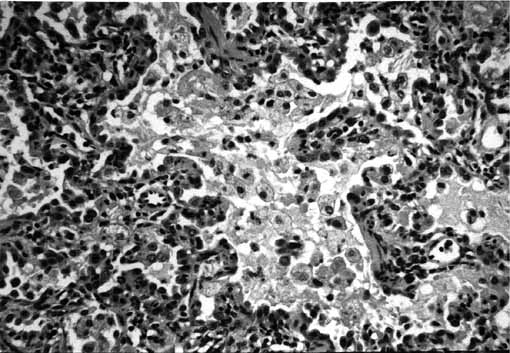

Figura 1: Aspecto de lesión muy celular con un patrón de afectación pulmonar difuso y homogéneo.